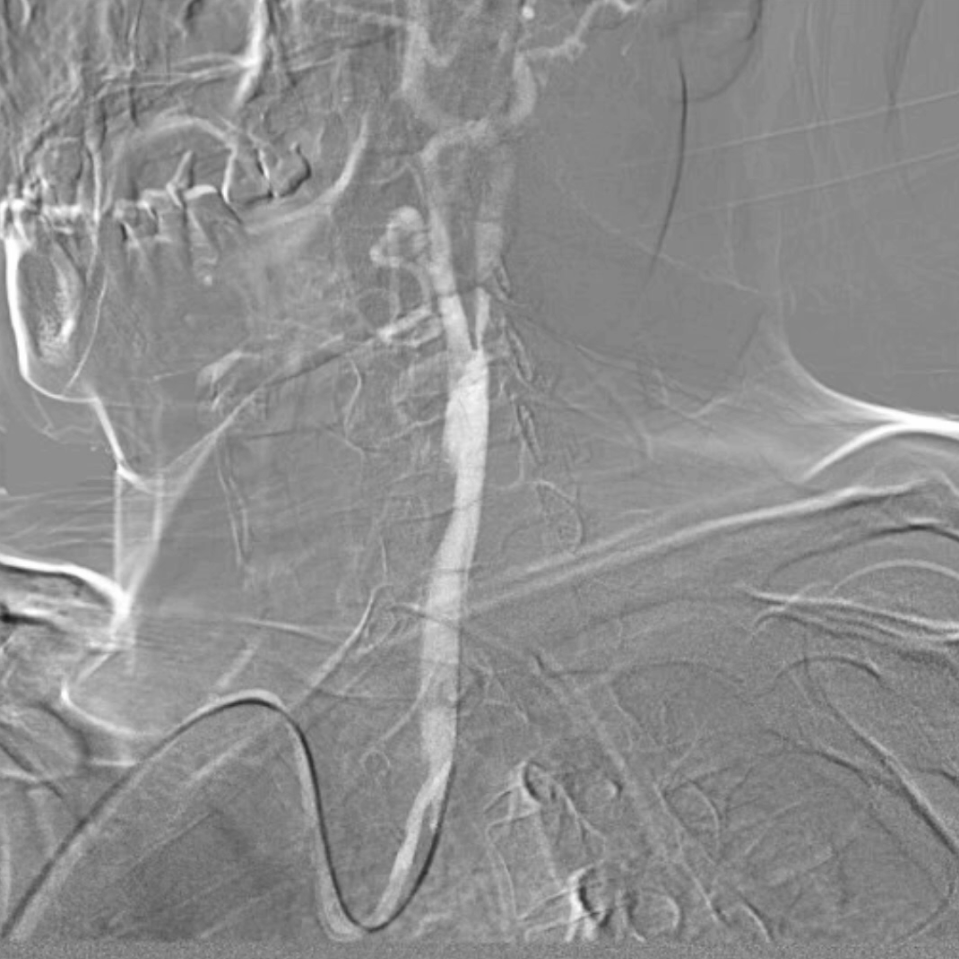

术后评估

血供改善与安全性验证

造影显示:支架膨胀良好,无需后扩张;

颅内血供:左侧颈内动脉血流通畅,因右侧闭塞,左侧成为全脑主要供血通路,血供恢复满意